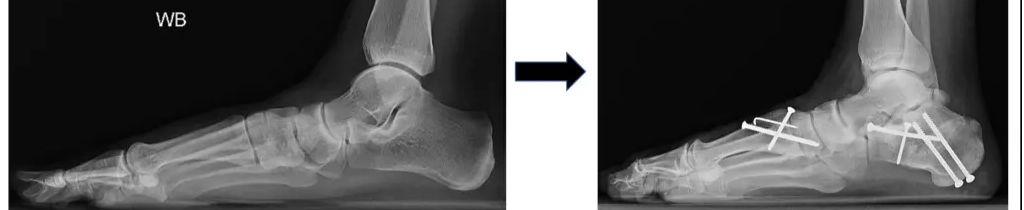

Flatfoot reconstruction is a comprehensive surgical approach used to treat painful adult-acquired or congenital flatfoot deformity associated with tendon dysfunction, instability, and progressive collapse of the arch.

Flatfoot reconstruction typically involves a combination of procedures, which may include tendon repair or transfer, osteotomies, ligament reconstruction, and in severe cases, hindfoot fusion.